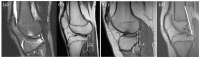

The incidence of anterior cruciate ligament injuries in skeletally immature patients has increased in recent years. The gold standard treatment of this type of trauma in children is not yet established. Conservative management may underestimate the risk of new meniscal and chondral tears; on the other hand, a more interventional approach may expose the patient to iatrogenic damage to the growth plate. A correct approach to the skeletally immature patient with knee trauma is therefore essential to guide the decision-making process. This review article aims to present an update on the epidemiology and diagnostic process of pediatric patients with anterior cruciate ligament tears and possible associated injuries. Level of Evidence: V.